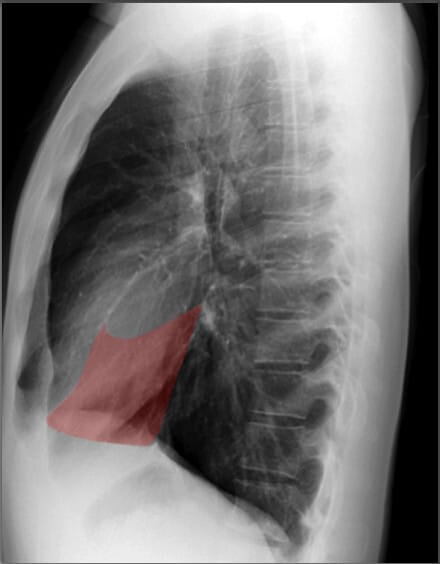

Lateral View of Chest X-ray

측면 영상은 폐, 심장 및 척추의 깊이를 평가하는 데 유용합니다.

| 늑골횡격막각 (Costophrenic Angle) |

| ✅ 늑골과 횡격막이 만나는 각도로, 정상적으로 뚜렷하고 예리하게 보여야 합니다. 둔해지거나 소실되면 흉수(pleural effusion) 가능성을 시사합니다. |